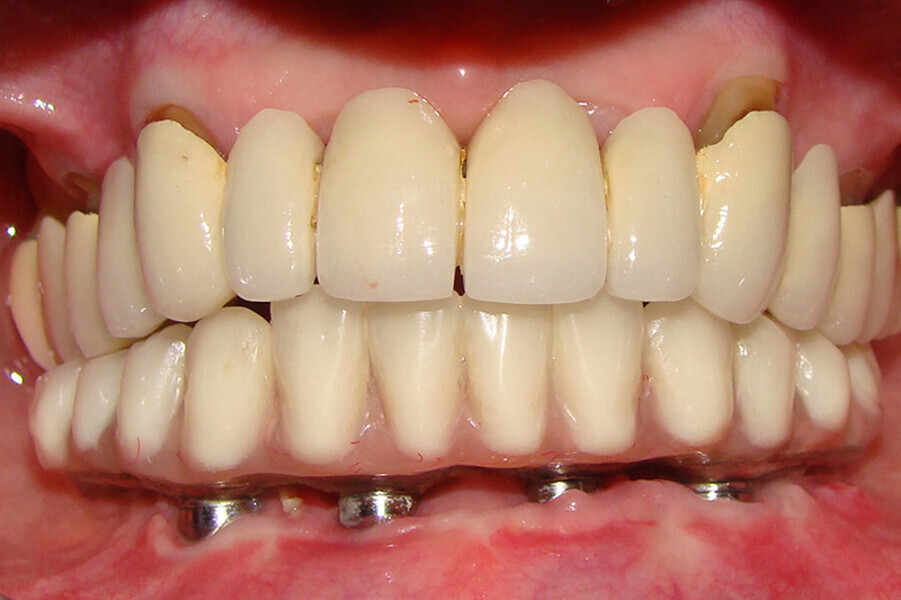

Fig. 4 Prótesis Híbrida inmediata y radiografía control con 6 años post-operatorio

Fig. 5. Prótesis Híbrida inmediata y radiografía control con 6 años post-operatorio

Fig. 6. Prótesis Híbrida inmediata y radiografía control con 6 años post-operatorio